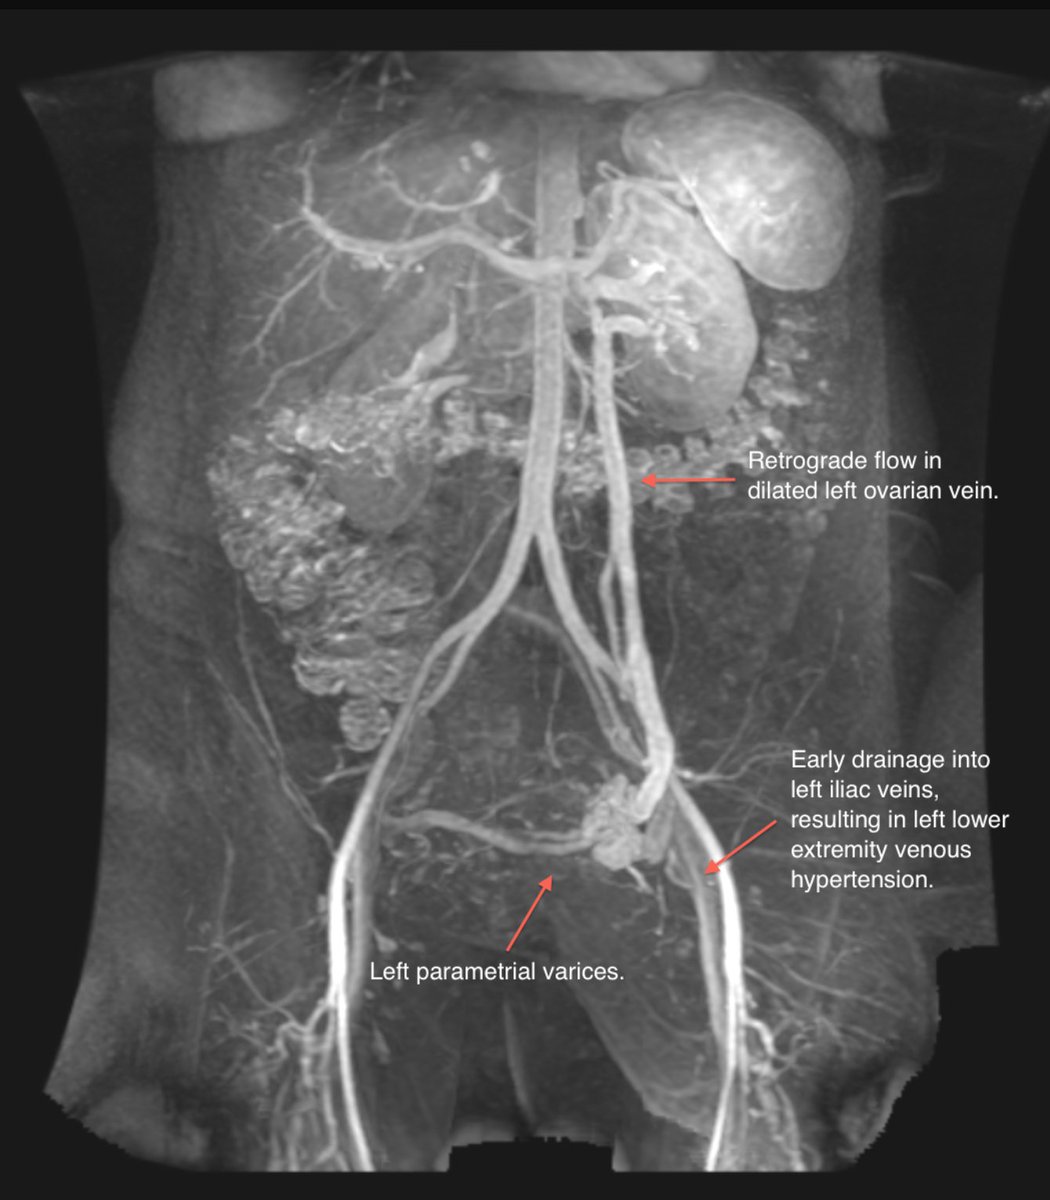

Varicose veins include the labia / buttock? Think pelvic congestion. Get MRV. Look for reflux / collaterals (credit Stanford Medicine) #FOAMed